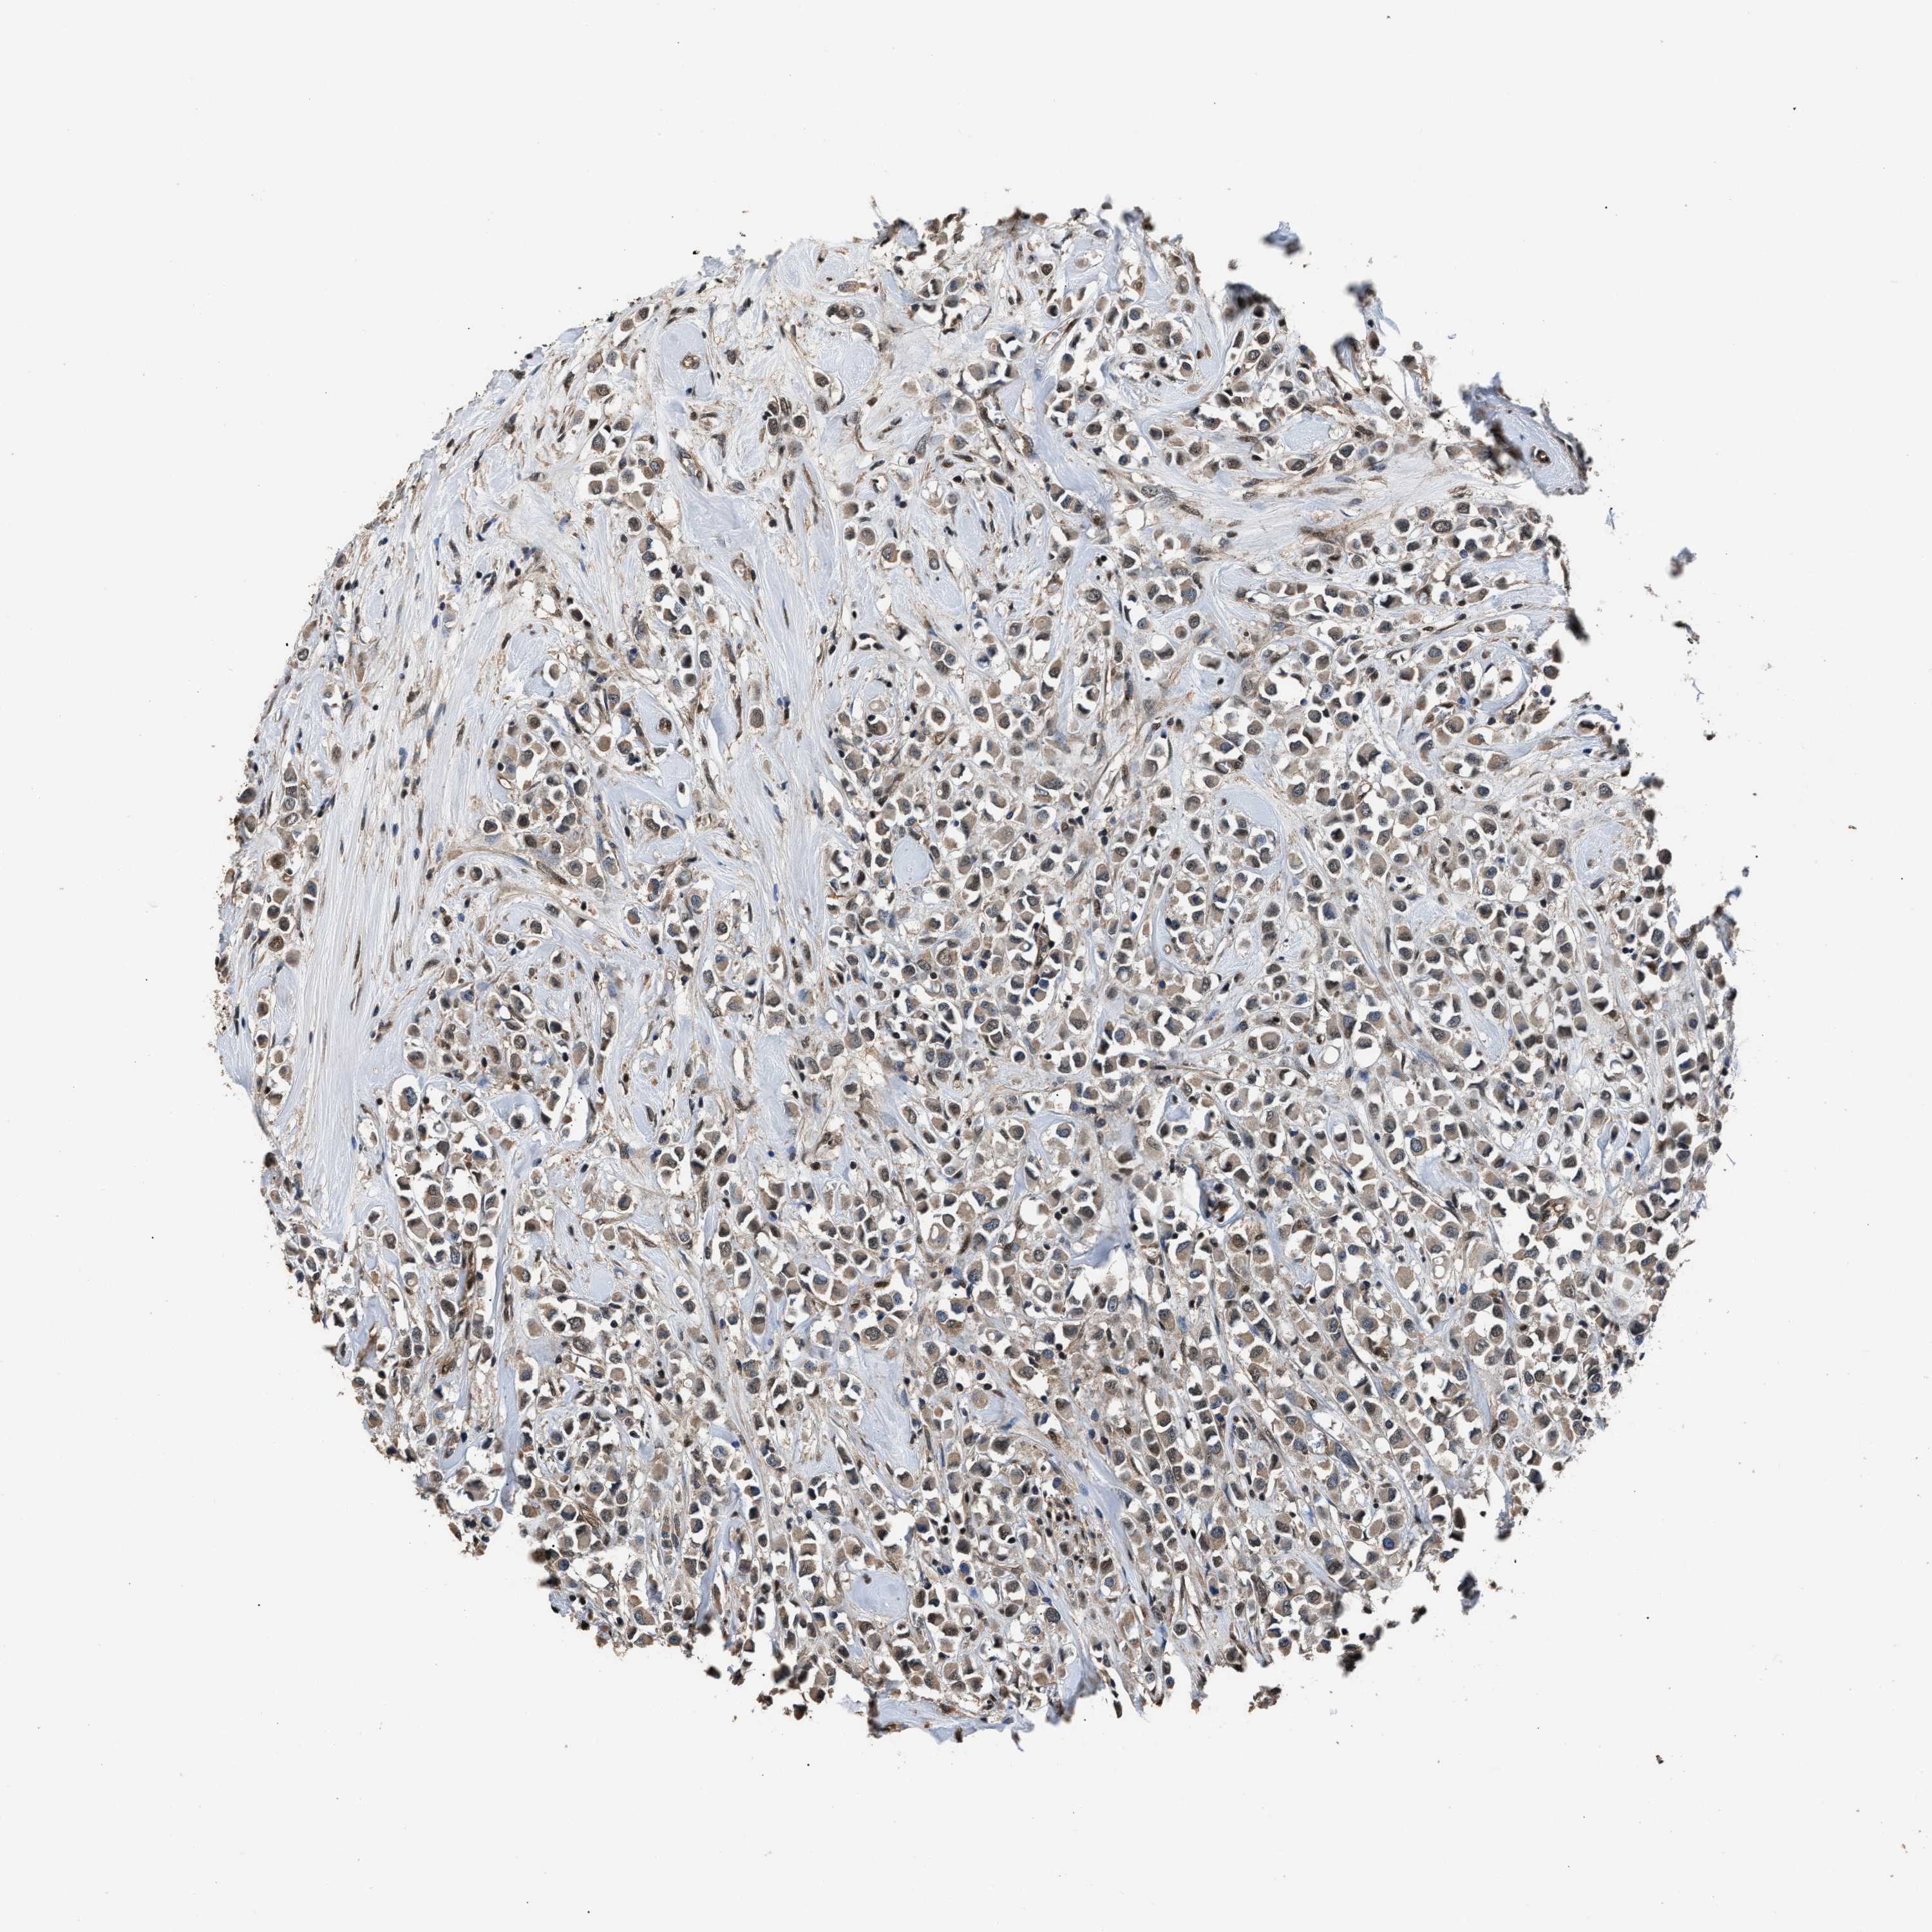

CANCER BREAST CANCER Show tissue menu

BRCA TCGA BRCA VALIDATION PROTEIN EXPRESSION